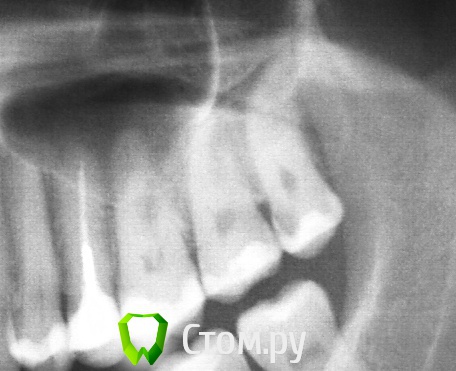

Чертков Александр Опубликовано 31 октября, 2013 Поделиться Опубликовано 31 октября, 2013 Ага. Сегодня добыл )) Красавчик! ( И доктор и зуб...) Наверняка в нем 5 к\к...мечта эндодонта... Ссылка на комментарий

Большой Зеленый Опубликовано 31 октября, 2013 Поделиться Опубликовано 31 октября, 2013 Красавчик! ( И доктор и зуб...) Наверняка в нем 5 к\к...мечта эндодонта...Страшный сон терапевта..) Ссылка на комментарий

M@estro Опубликовано 31 октября, 2013 Поделиться Опубликовано 31 октября, 2013 Трубопровод! Сильно! Ссылка на комментарий